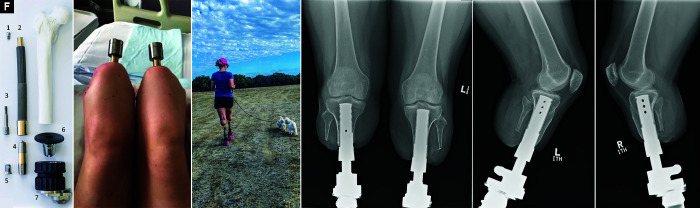

Background: Transcutaneous osseointegration following amputation (TOFA) is an alternative to standard prosthesis by directly anchoring a metal implant to the skeletal residuum. However, there is a paucity of data concerning whether TOFA is safe and reasonable for patients with lower limb amputation to manage complications of sepsis. The primary aim of this study was to record adverse post-TOFA events for nine patients (15 limbs) whose index amputations were performed to manage sepsis-related complications. The secondary aim was to compare the pre- and post-TOFA mobility and quality of life (QoL).

Methods: A retrospective review of our practice's prospectively maintained osseointegration database was performed. Patients with transfemoral and/or transtibial osseointegration for a limb in which the original amputation was performed to manage sepsis, at least two years prior to the study date, were included. This yielded nine patients with 15 osseointegrated limbs. Adverse events were antibiotics for infection or unplanned surgery. Outcomes were recorded using the SF-36 Health Survey and the Questionnaire for persons with a transfemoral amputation. Formal mobility evaluations included a 6-minute walk test and physician-determined K-levels.

Results: The cohort had a mean age of 42.8 ± 6.5 (range: 35.0-52.4) years. The mean body mass index (BMI) was 27.2 ± 11.0 (18.4-54.5). Six patients (67%) underwent bilateral osseointegration, and three (33%) patients underwent unilateral osseointegration. Six patients (67%) representing 12 limbs (80%) had an uneventful course post-osseointegration. One (11%) patient had intravenous antibiotics to manage a superficial infection. One (11%) other patient had a periprosthetic femur fracture managed by open reduction internal fixation. No systemic complications, additional surgeries, or implant removals occurred. 75% (6/8) achieved K-level ≥ 2 post-osseointegration. There was no significant change in the 6-minute walk test.

Conclusion: Lower limb osseointegration is a safe and effective rehabilitation option for patients whose amputations were a result of sepsis.

Clinical significance: Further judicious use of TOFA for these patients seems highly merited.